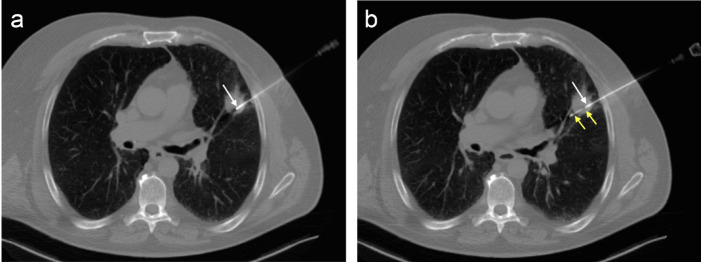

Purpose: Percutaneous biopsy has demonstrated high accuracy in diagnosis of lung nodules, but the technique is not innocuous and a yield decrease in lesions smaller than 20 mm has been reported. We carried out a prospective study to evaluate and compare the complications and efficacy of percutaneous core needle biopsy (CNB) of solitary solid lung nodules, which were performed with two types of automatic guns.

Methods: 330 consecutive CT-guided CNB were included. Tru-cut or end-cut 18G devices were used alternatively. Nodules were categorized by their size: ≤10 mm, 11-20 mm and >20 mm. Incidence of complications such as pneumothorax or hemoptysis and factors influencing them (nodule size and depth within lung parenchyma) were evaluated. Diagnostic accuracy of CNB achieved in the three groups of nodules regarding the two different needles were calculated and statistically evaluated and compared.

Results: We performed 68 CNB in nodules ≤10 mm, 130 in 11-20 mm and 132 in >20 mm. Pneumothorax appeared in 24.2% of them, but only 5.7% required drainage. Hemoptysis was developed in 9.4% and abundant hemoptysis with hypoxemia was observed in only 4.2% of patients. Regarding appearance of complications between the two needle types, no significant differences were found. A higher risk of hemoptysis was observed in nodules ≤10 mm (OR = 3.87; 95% CI = 1.24-12.06, P = 0.019) and in those located deeper in pulmonary parenchyma (OR = 2.21; 95% CI = 1.04-4.69, P = 0.038). End-cut needles reached a diagnostic accuracy of 93.7%, 92.1% and 98.3%, in nodules sized ≤10 mm, 11-20 mm and >20 mm, respectively. Corresponding results for tru-cut were 84.7%, 88.5% and 92.1%. In spite of differences reaching up to 9% in smaller nodules, intra-group results were not significant.

Conclusion: Both needles have similar complications rate. Despite not having observed statistically significant differences between the two types of needles, end-cut devices have demonstrated a higher diagnostic yield in the three groups of nodules and could be a more suitable option especially for CNB of nodules ≤10 mm.